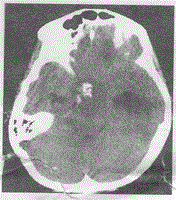

问题 男,17岁,头痛半年,头颅CT平扫如图所示,最可能的诊断是

选项 A.垂体瘤 B.颅咽管瘤 C.海绵状血管瘤 D.脊索瘤 E.蛛网膜囊肿

答案 B